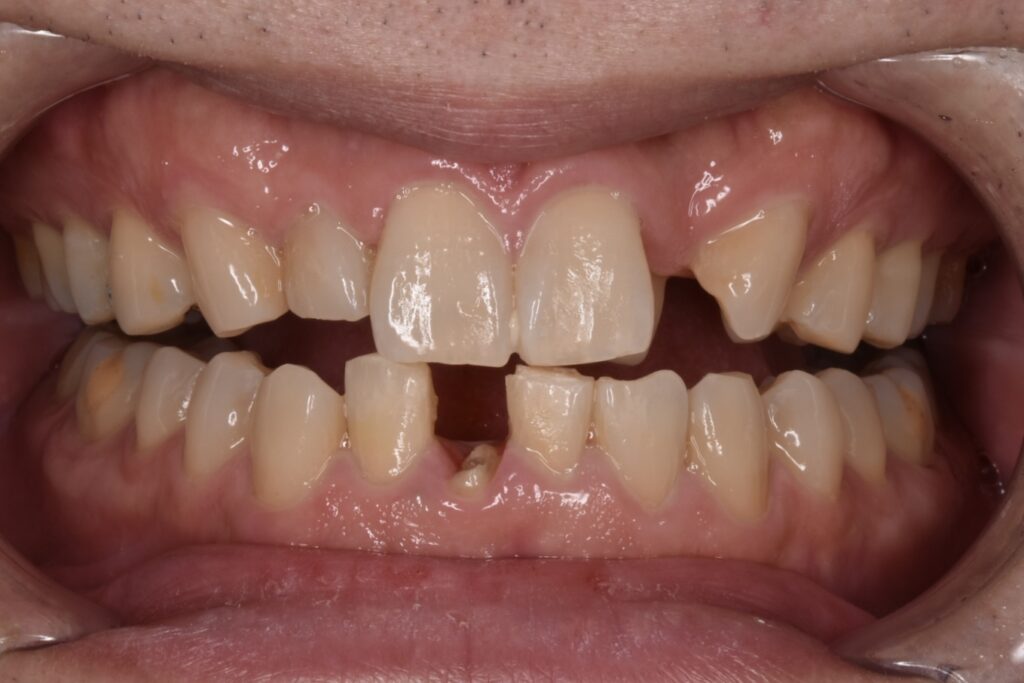

50代男性 下の前歯が東京の歯科で一年ほど前に作られた差し歯で、今回はそれが取れてしまったとご相談いただきました。検査の結果、歯が土台ごと折れていました。折れている場所が歯茎の中の方で折れていて、歯槽骨ギリギリの場所です。

歯が破折していることに大変ショック受けられていました。丁寧にお話を伺い費用をかけてでもご自身の歯をもう一度使えるなら自分の歯でできるだけ過ごしたいと仰ってくださいました。